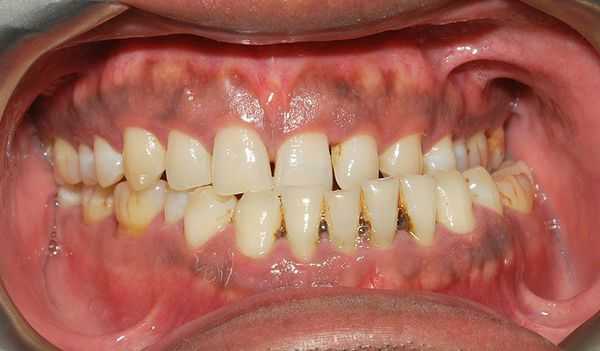

Глубокий прикус, скученность, сужение зубных рядов, эффект Попова Годона, смещение центральной линии, генерализованный пародонтит, протрузия, адентия

Начальная степень глубокого прикуса выражается образованием небольших эстетических дефектов передних зубов - трещинки, мелкие сколы эмали.

Глубокий прикус средней тяжести - интенсивное стирание эмали на внутренней стороне верхних зубов и на внешней стороне зубов нижней челюсти.